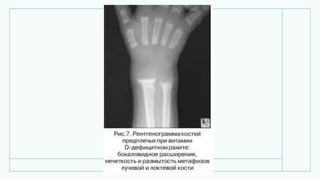

• Рентгенограмма верхньої

кінцівки дитини 7 місяців:

витончення и розгалуження

волокон кортикального шару

кісток передпліччя.

• Рентгенограмма верхньої кінцівкидитини 7 місяців: витончення и розгалуження волокон кортикального шару кісток передпліччя.